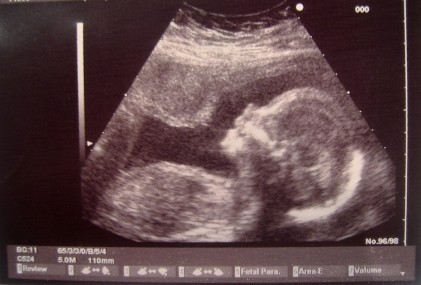

L’heureux élu du club de Léo Messi est sans doute le plus jeune joueur recruté à ce jour. L’équipe Catalane vient en effet de mettre la main sur un prometteur fœtus allemand de 29 semaines dont le prénom reste pour l’instant toujours inconnu, repéré par un recruteur du FC Barcelone au sein d’un centre gynécologique de Bavière.

Si le choix du FC Barcelone de miser sur un talent aussi précoce peut paraître excessif au regard de certains, il s’agit avant tout d’un choix stratégique tout à fait légitime. Carles Folguera est le directeur de la Masia, le centre de formation du club qui devrait prendre en charge cette nouvelle recrue dès sa venue au monde : « On a eu confirmation de sa capacité à lancer de très bonnes frappes du pied au cours de multiples échographies. Le potentiel est là et c’est notre devoir en tant que club d’élite de signer un joueur quand on décèle du potentiel chez lui. L’idée, c’est d’éviter de passer à côté d’un génie du foot qui pourrait finir entre les mains d’une autre formation. »